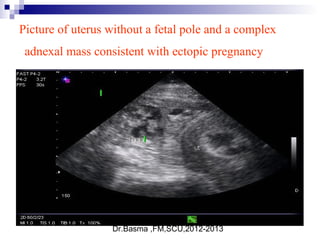

Picture of uterus without a fetal pole and a complex

adnexal mass consistent with ectopic pregnancy

ultrasonographic diagnosis

 Definitive ultrasonographic diagnosis of an ectopic pregnancy is made in

only about 20% of cases, when an extrauterine pregnancy is clearly

identified (ie, an extrauterine gestational sac with a yolk sac or fetal pole is

visualized).

 numerous findings that are highly suggestive of ectopic pregnancy,

including

1. an empty uterus in a patient with a β-hCG level above the discriminatory

zone,

2. an adnexal mass other than a simple cyst .

3. echogenic fluid in the cul-de-sac, or anything more than a small amount of

fluid in the cul-de-sac.